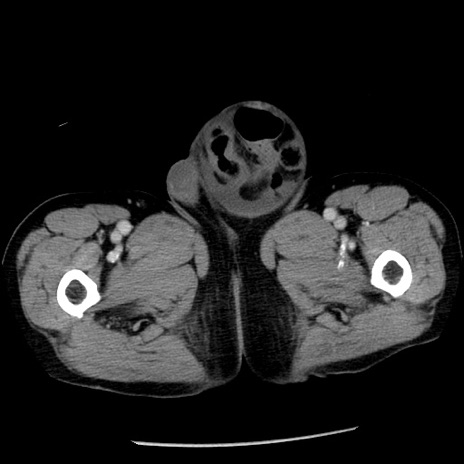

冠状断像

【症例】80歳代男性

【主訴】嘔吐

【現病歴】昨晩2回嘔吐あり、今朝になっても嘔吐あり。来院。

【既往歴】胃潰瘍

【身体所見】意識清明、BT 37.6℃、BP 166/95mmHg、HR 100bpm、SpO2 97%、腹部:平坦・軟、腸蠕動音聴取良好、圧痛なし。

【データ】WBC 21900、CRP 1.46